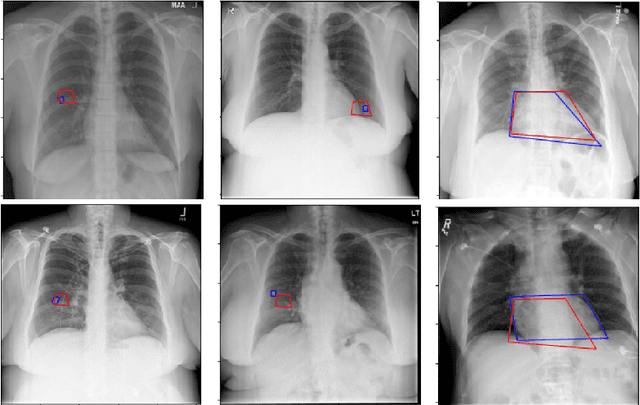

Medical image analysis practitioners have embraced big data methodologies. This has created a need for large annotated datasets. The source of big data is typically large image collections and clinical reports recorded for these images. In many cases, however, building algorithms aimed at segmentation and detection of disease requires a training dataset with markings of the areas of interest on the image that match with the described anomalies. This process of annotation is expensive and needs the involvement of clinicians. In this work we propose two separate deep neural network architectures for automatic marking of a region of interest (ROI) on the image best representing a finding location, given a textual report or a set of keywords. One architecture consists of LSTM and CNN components and is trained end to end with images, matching text, and markings of ROIs for those images. The output layer estimates the coordinates of the vertices of a polygonal region. The second architecture uses a network pre-trained on a large dataset of the same image types for learning feature representations of the findings of interest. We show that for a variety of findings from chest X-ray images, both proposed architectures learn to estimate the ROI, as validated by clinical annotations. There is a clear advantage obtained from the architecture with pre-trained imaging network. The centroids of the ROIs marked by this network were on average at a distance equivalent to 5.1% of the image width from the centroids of the ground truth ROIs.